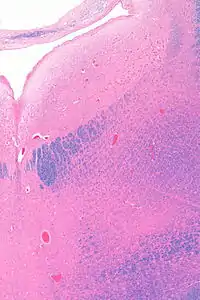

![]() Micrograph showing the locus coeruleus. HE-LFB stain. | |

The locus coeruleus (LC) is located in the posterior area of the rostral pons in the lateral floor of the fourth ventricle. It is composed of mostly medium-size neurons. Melanin granules inside the neurons of the LC contribute to its blue colour. Thus, it is also known as the nucleus pigmentosus pontis, meaning "heavily pigmented nucleus of the pons." The neuromelanin is formed by the polymerization of norepinephrine and is analogous to the black dopamine-based neuromelanin in the substantia nigra.